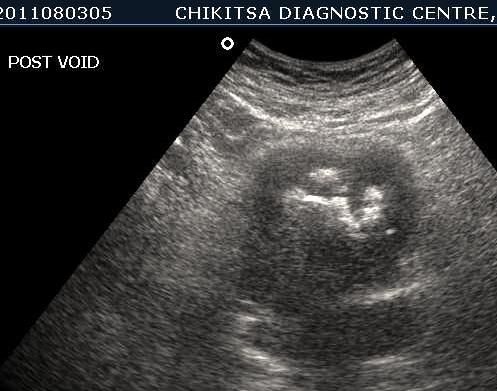

March 2012 :

5 5 cm x 5 cm size  ill-defined heterogeneous area in the posterior wall of the urinary bladder which is thickened and measures upto 0.6 cm in thickness. Large solid calcific areas are noted in the thicknened portion of the wall urinary bladder.  Suggestive of schistosomiasis of the  urinary bladder (possibly with malignant change).

Left kidney shows hydronephrosis.